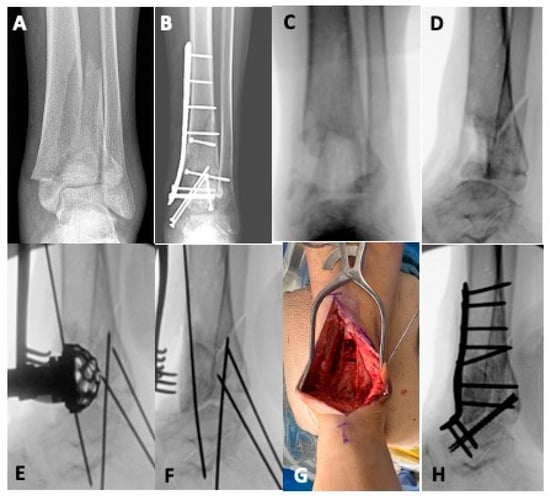

The Impact of Fibular Fixation Method on Pilon Fracture Healing

Background: Pilon fractures are associated with high-energy injuries, and there is presently much debate as to optimal fixation strategies and timing of intervention. There is little evidence comparing the type of fibular fixation during pilon fracture fixation. The purpose of this study was [...] Read more.

Background: Pilon fractures are associated with high-energy injuries, and there is presently much debate as to optimal fixation strategies and timing of intervention. There is little evidence comparing the type of fibular fixation during pilon fracture fixation. The purpose of this study was to compare fibular fixation methods in complex pilon injuries as it relates to pilon union rates and development of post-traumatic arthritis. Methods: This was a retrospective review from an urban Level 1 trauma center from January 2009 to May 2019, including patients age ≥ 18 who sustained a pilon fracture with an associated fibula fracture. Patients were allocated into one of three groups based on fibular fracture treated with plating, intramedullary device, or no fixation. Radiographic analysis was performed postoperatively and at final follow up to evaluate for tibial or fibular nonunion, malunion, talocrural angle, and ankle Kellgren–Lawrence grade. Results: Of the 107 patients in this study, 42 underwent surgical fixation of their fibular fracture. There were no differences with respect to tibial or fibular union rates amongst the three groups. Furthermore, there were no differences in the presence of radiographic ankle arthritis at final follow up. However, Kellgren–Lawrence arthritis grading did appear to be a more severe grade in patients who did not undergo fibular fixation (p = 0.001). Conclusions: Fibular intramedullary fixation does not appear to influence tibial or fibular nonunion rates as compared to plating in complex pilon injuries. Full article